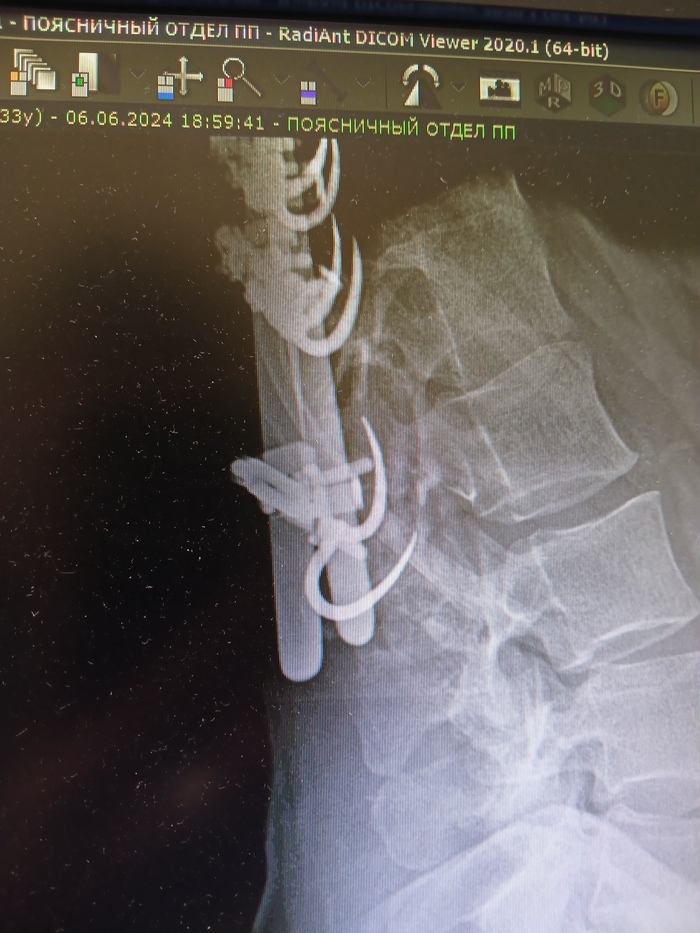

Думаете, это все? Хуюшки сказал заюшка. Через год (2007) выяснилось, что мне неправильно поставили крючок. Пришлось переделывать. Когда только-только все зажило, и я едва смогла нормально дышать, выясняется такое... Отрицание, гнев, торг, депрессия – все было. Очень тяжело далось мне это, родителям так и подавно. Но ничего, поправили. Получилось как-то так

Как шмогли. Но стало лучше, ибо страшно мешал, а потом норм. Фото новое, но с тех пор ничего не менялось

Это фото со снимка, но не 2009, 2014 год, по традиции, сделано на тапок

Внимание на верхушку, она поехала, видите? Грубо говоря, негерметично стоит

Вот они 2 штучки, они со мной навечно. Я сгнию, они останутся 😁 Снимок со стороны груди